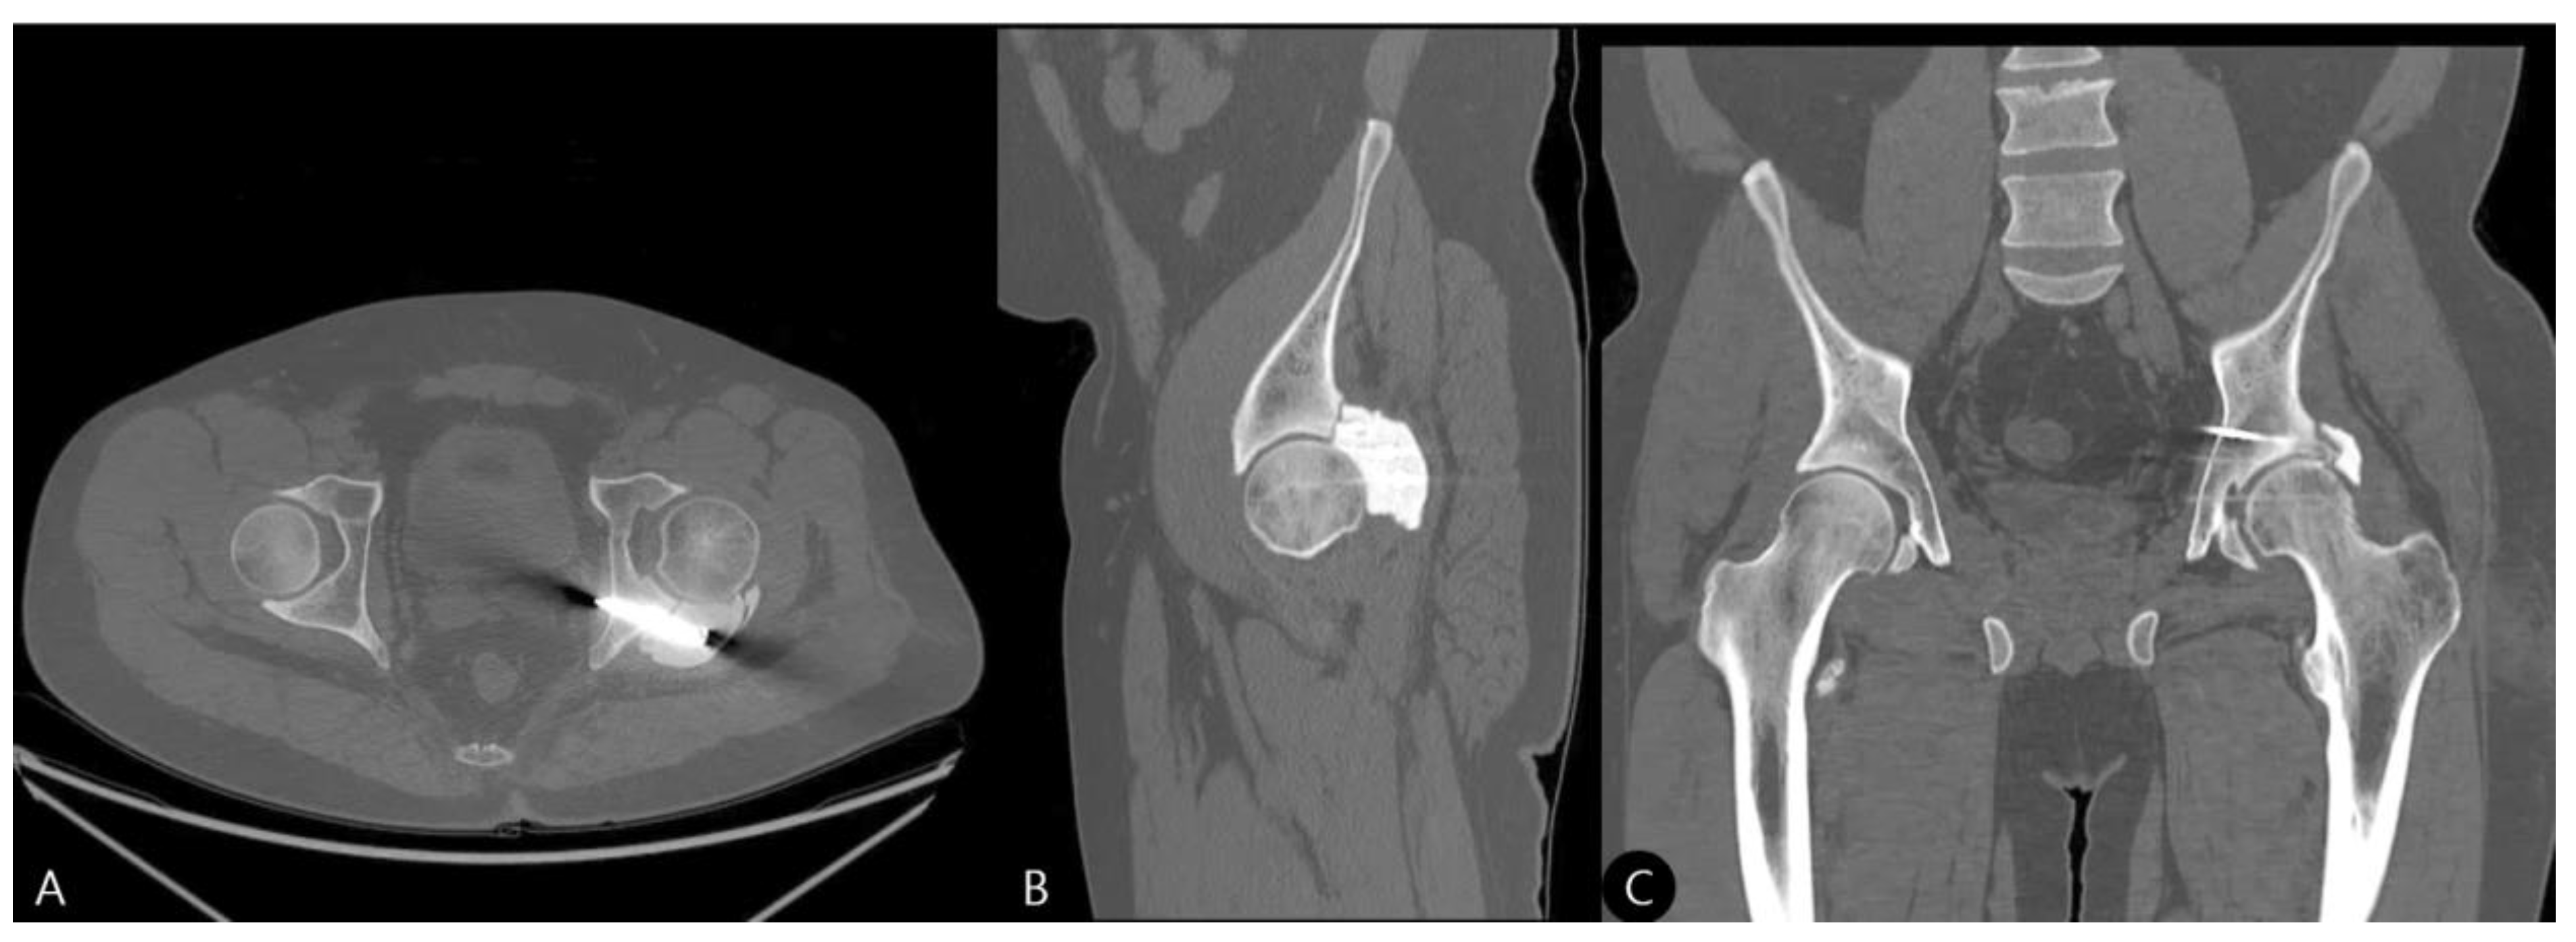

- 15 Months: A CT scan showed a stable joint, concentric reduction, and no signs of screw loosening or osteolysis (Figure 8). The patient reported no functional limitations. The mHHS was 82/100.